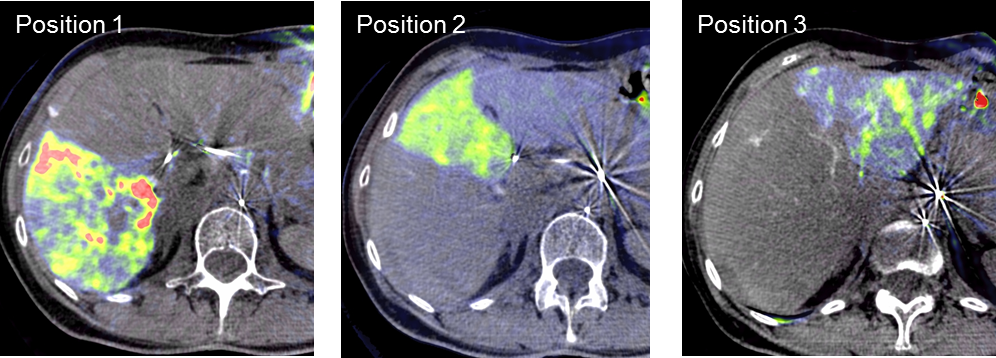

Selektive Interne Radio-Therapie (SIRT)

Die Selektive Interne Radiotherapie (SIRT) wird in der Fachliteratur auch Radioembolisation (RE) genannt. Hierbei werden gezielt kleine, radioaktive Kügelchen, sog. Mikrosphären, über den Katheter (siehe TACE) von mehreren Positionen in der Leber mit dem Blutstrom in das gut durchblutete Tumorgewebe gebracht und bleiben dort in den kleinen Gefäßen "stecken", die den Tumor ernähren. Von dort bestrahlt das in den Kügelchen enthaltene radioaktive Element Yttrium-90 über mehrere Tage hinweg das Tumorgewebe und zerstört es selektiv. Dieses Verfahren kann bei Leberkrebs oder -metastasen eingesetzt werden, wenn die Herde trotz Chemotherapie weiter wachsen und nicht chirurgisch oder mittels RFA und TACE behandelbar sind.

Das Verfahren wird von der interventionellen Radiologie zusammen mit der Partnerabteilung der Nuklearmedizin sowie den entsprechenden Partnerkliniken geplant und durchgeführt.